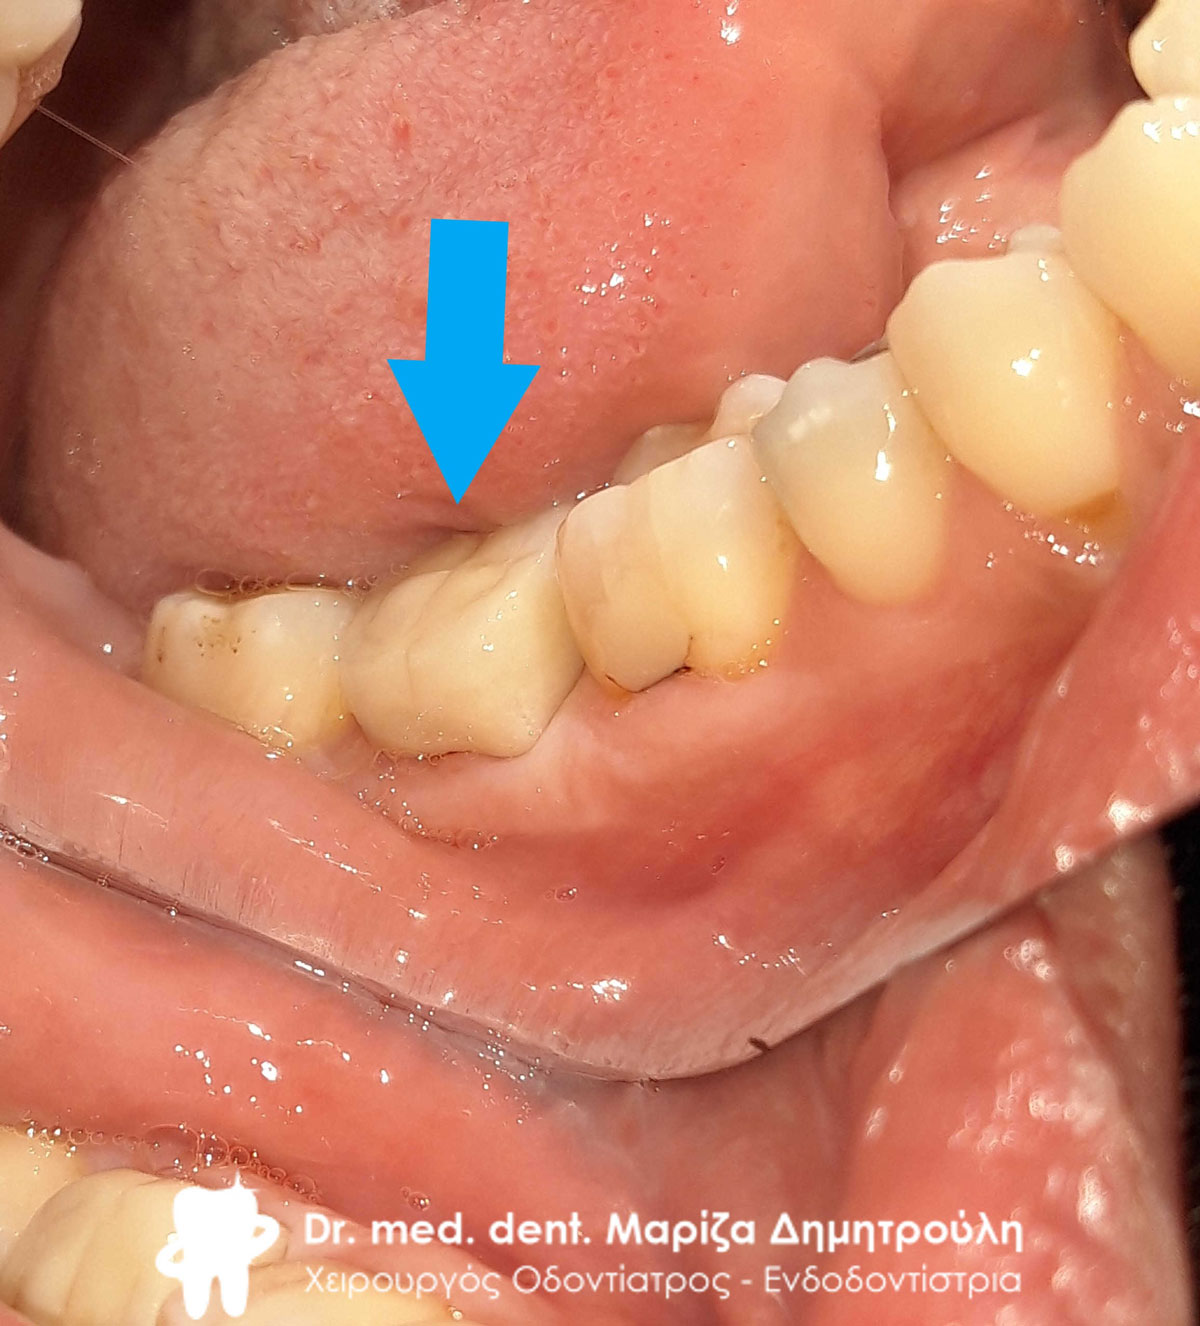

Αρχική κλινική εικόνα της αριστερής πλευράς της κάτω γνάθου

Αρχική κλινική εικόνα της αριστερής πλευράς της κάτω γνάθου

Αρχική κλινική εικόνα της αριστερής πλευράς της κάτω γνάθου

Αρχική κλινική εικόνα της αριστερής πλευράς της κάτω γνάθου

Αρχική κλινική εικόνα της αριστερής πλευράς της κάτω γνάθου